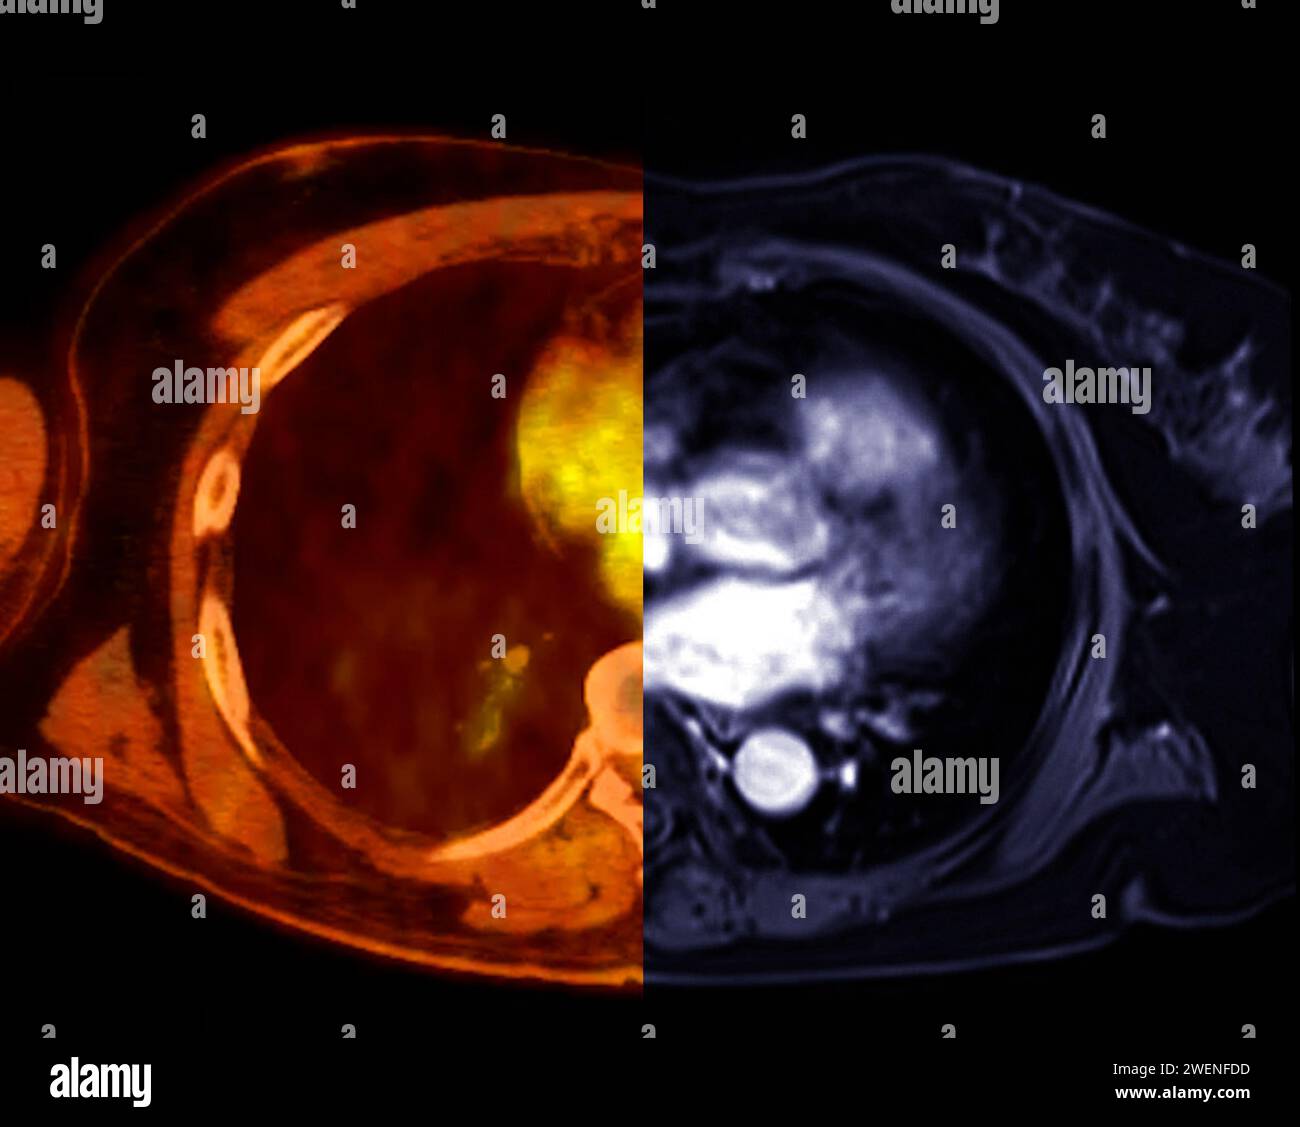

Moderne Bildgebung des Lungenhilus | Die Radiologie

Computertomografie | Moderne Bildgebung des Lungenhilus | springermedizin.de